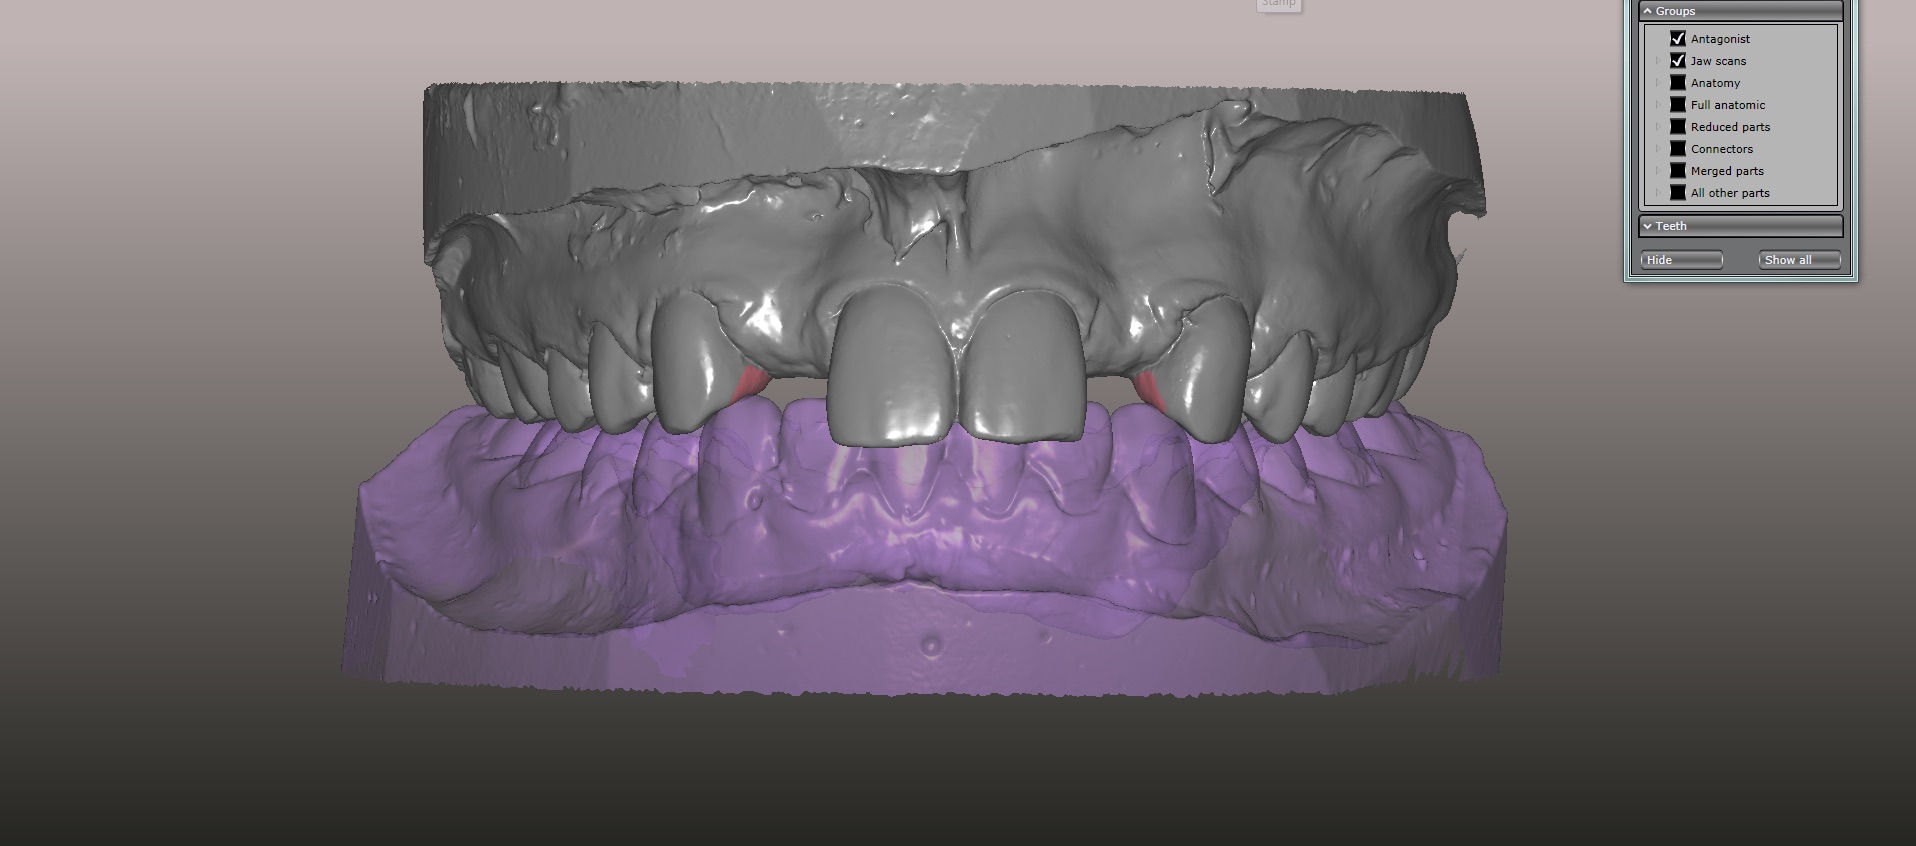

An approach utilizing CAD/CAM was employed to fabricate an accurate fitting, retentive, and esthetic ceramic single-wing resin-bonded bridge. Impressions were taken of the patient and scanned in the laboratory using maximum intensity projection. The scanned models were then used to design the final prosthetic frames utilizing EXOCAD software. The retainer positions and extensions were designed on the models based on the occlusal clearance (Figure 15). Next, the replacement tooth forms were chosen from a virtual library (Figure 16), and try-in PMMA bridge prototypes were milled in Primotec USA PMMA. This allowed for try-in of the design, adjustment of the contacts, and intraoral evaluation of the ridge contact (Figure 17). Once tried and idealized for both fit and occlusion, the design was sent back to the lab to rescan. Utilizing the software, a cut back was made on the lateral incisor (Figure 18), and a 0.3mm space was also virtually designed on the internal surface of the retainer wing to allow layering with feldspathic ceramic (Figure 19). The 0.2 mm internal edge of the wing was designed to be left intact to allow for precise seating and verification of fit on the model. After the frame was milled in zirconia (Zirconzahn, Prettau), it was verified on the model, and high fusing margin porcelain (Noritake CZR) was mixed with a clear utility wax and applied to the internal 0.3 mm depression. This was baked in the oven at a high temperature, allowing the wax to burn out and leaving the feldspathic ceramic fused to the internal surface of the retainer. Once cooled, this was checked for precise fitting on the model and adjustments were made to ensure full seating.

(15.) Models mounted in maximum intensity projection, allowing design of the retainer extensions on the lingual of the canines (in pink).

Figure 15